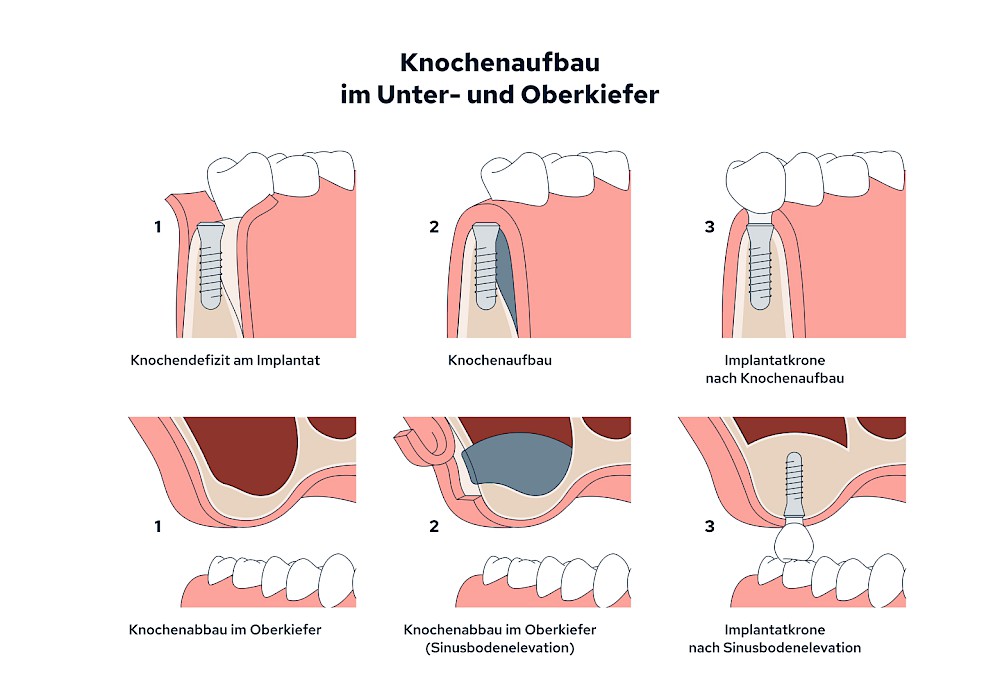

Knochenaufbau und Implantateinsatz

Ist nicht genügend Knochen zur Verankerung eines Implantates vorhanden, kann über einen sogenannten Knochenaufbau die Möglichkeit für das Einbringen eines Implantates geschaffen werden. Dazu kann z.B. Knochen aus der Kieferwinkelregion oder auch aus der Kinnregion entnommen und im Bereich der Fehlstellen aufgetragen werden. Auch künstliches Knochenmaterial kann dabei zum Einsatz kommen.

Im Oberkiefer wird – wenn ein Knochenaufbau notwendig ist – der Knochen in der Regel nicht außen "aufgelegt", sondern es wird der Boden der Kieferhöhle entweder über den Implantat-Bohrkanal durch Verdichtung nach oben gedrückt (interner Sinuslift) oder über eine Fensterung der vorderen knöchernen Kieferhöhlenwand kann Knochen im Bereich des Kieferhöhlenbodens eingebracht (externer Sinuslift).